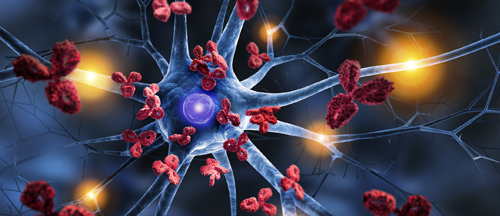

The National Cancer Institute is looking for clinical trial participants with Glypican-3 positive HHC, a type of liver cancer, to receive an experimental therapy of genetically modified CAR-T cells. Study treatment consists of a preparative regimen with standard chemotherapy drugs fludarabine and cyclophosphamide and CAR-T cell infusion. Researchers want to see if this treatment can help people with a certain type of liver cancer. NIH will cover study-related costs for medical care, travel and housing. For more information on specific inclusion and exclusion criteria, visit https://go.usa.gov/xtErY or call 866-444-2214 (TTY users dial 7-1-1) and reference study #21-C-0030.